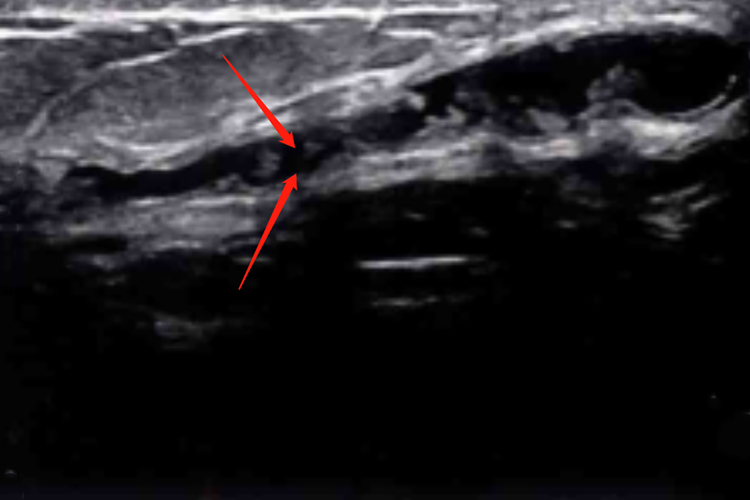

Ⅰ型:乳晕周边中央带腺体层大乳管单纯性扩张,导管壁光滑,无明显增厚,导管内可见点状极低回声,管腔内未见实性回声充填。